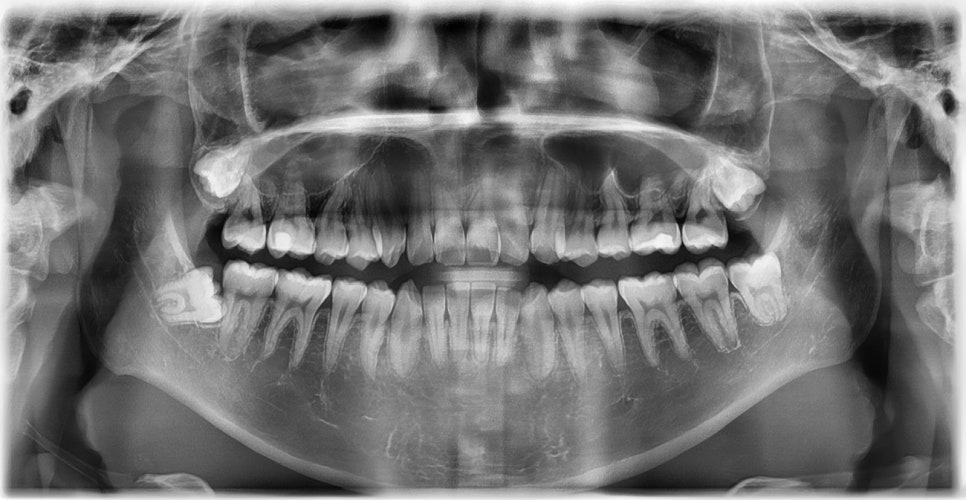

외관상으로는 아랫입술이 돌출되어 보이고 아래 치아가 좌측으로 치우치면서 치아 중심선(midline)이 맞지 않는 상태였습니다. 또한 환자는 어릴 적 넘어지면서 앞니가 깨졌던 외상 병력이 있었고, 그 영향으로 앞니 뿌리가 부분적으로 흡수된 상태였습니다.

2024.12. 초진 파노라마 엑스레이 - 연세정원치과

정밀 검진 결과, 하악 치열이 좌측으로 틀어져 있었고 그로 인해 위아래 치아 중심선이 일치하지 않았습니다. 아래 치열이 전체적으로 전방 위치하여 아래 입술 돌출이 더 도드라져 보이는 상태였습니다. 그리고 상악궁이 하악궁보다 좁아서 앞니 부위 일부 반대로 물리는 치아 교합도 관찰되었습니다. 특히 외상 치아의 경우, 교정력 적용시 추가적인 염증성 치근 흡수 위험이 존재하기 때문에, 치료 중 지속적인 관찰이 필수적인 상황이었습니다.